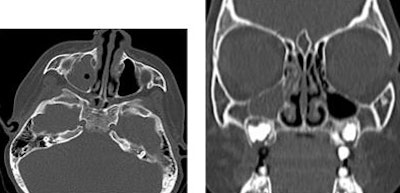

![]() |

| MDCT spine images of a 1-year-old trauma patient show left vertebral artery dissection. |